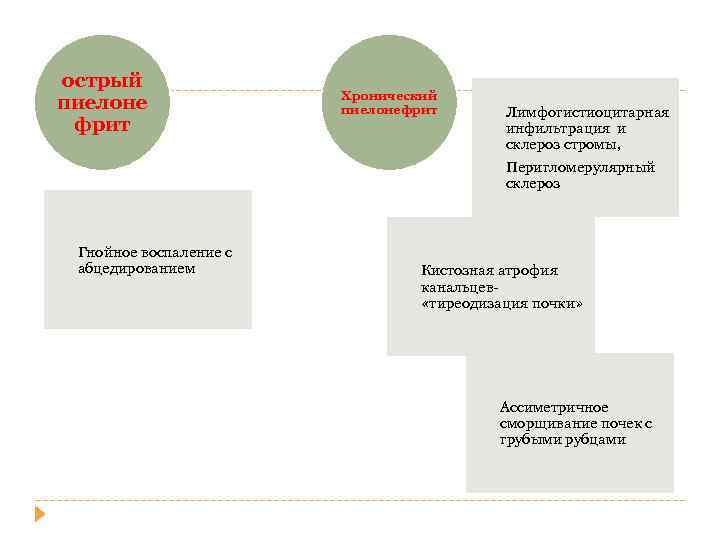

острый пиелоне фрит Гнойное воспаление с абцедированием Хронический пиелонефрит Лимфогистиоцитарная инфильтрация и склероз стромы, Перигломерулярный склероз Кистозная атрофия канальцев «тиреодизация почки» Ассиметричное сморщивание почек с грубыми рубцами